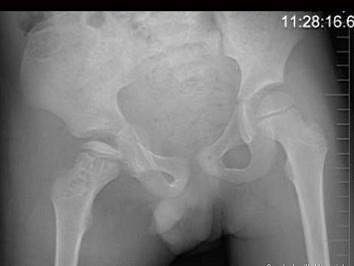

问题 7岁男孩,发现跛行半年伴疼痛,来科行双髋关节正位片,如图所示,最佳的诊断是 ( )

选项 A、克丁病 B、以上都不正确 C、右股骨头骨软骨炎 D、右侧扁平髋 E、右髋关节结核

答案 C